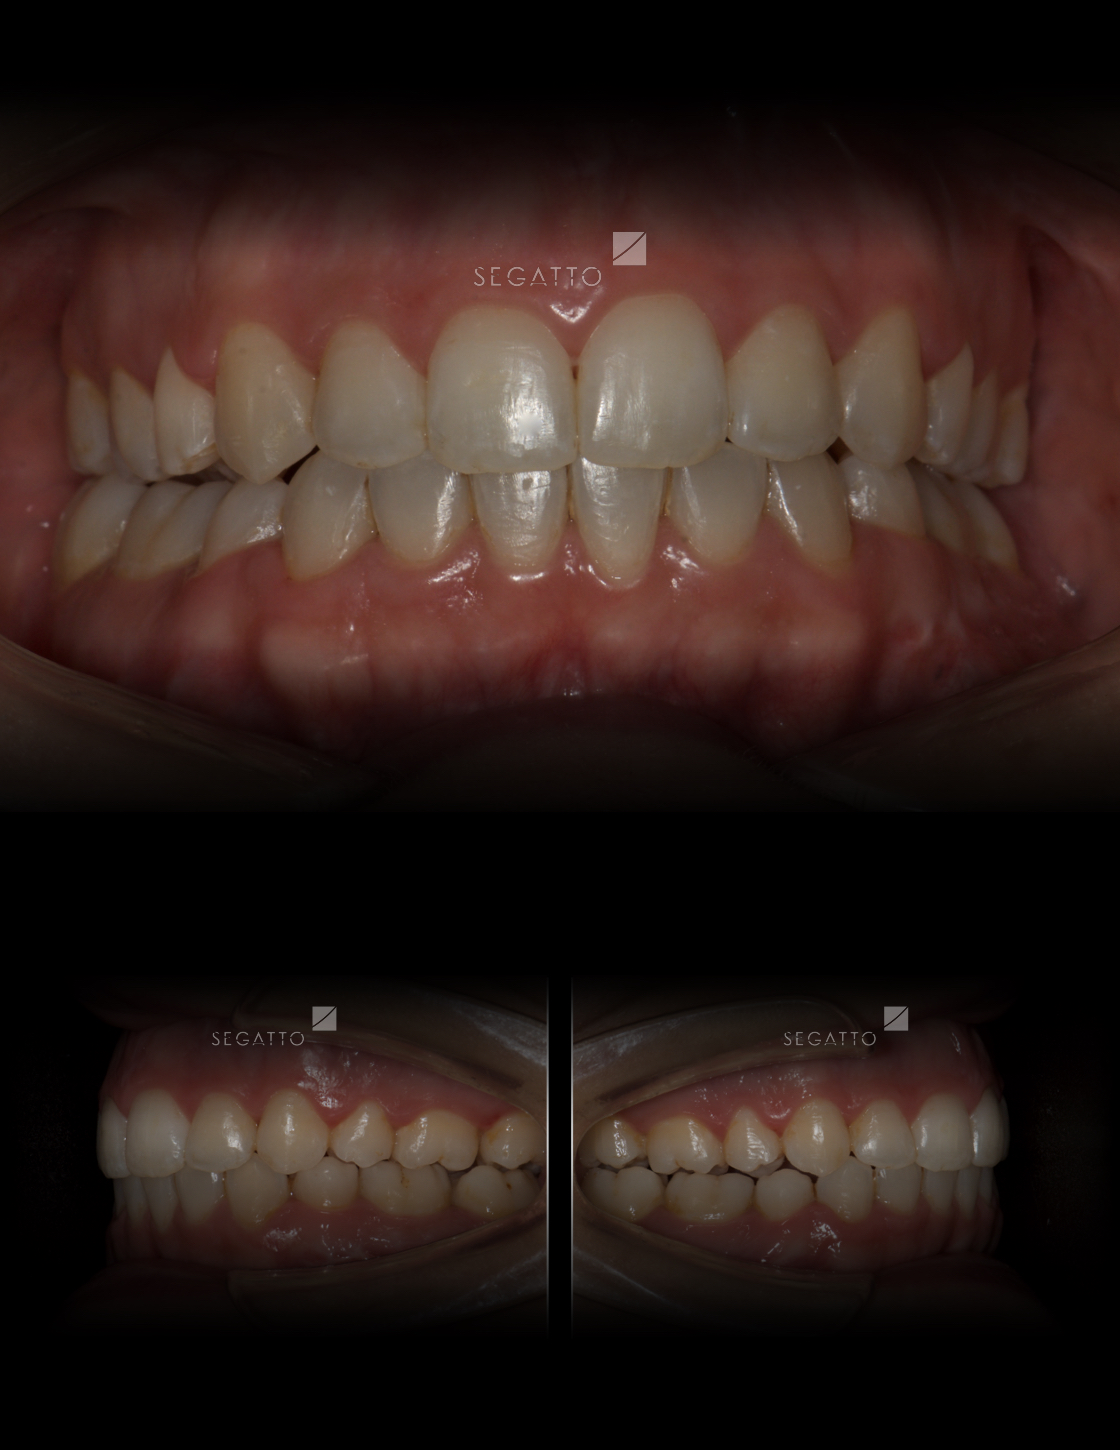

Orthodontics

Cases